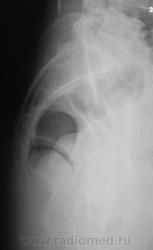

Боковая.

Посттравматический симфизит - это такой медицинский диагноз есть? Тогда уж лучше - симфизопатияУлыбаюсь.  По поперечному перелому Л5 - тангенциальный эффект, сложение теней. По хорошему, надо бы доснять поясничный отдел позвоночника, в том числе в косых проекциях - на дугоотростчатые суставы, и грудо-поясничный переход.

2. А на боковой массе крестца справа разве не линия консолидирующегося перелома?

Возможно перелом остистого, все-же был?

Возможно, перелом последнего копчикового тоже был?

Верятность перелома остистого отростка Л4 очень велика. Это находит подтвеждение и на боковом снимке.

Поздно заметил ветку.. увидел симфизит, перелом остистого L4, мазоль Co 5, и  конечно spina bifida S1 ))) глянуть бы межпозвоночные..